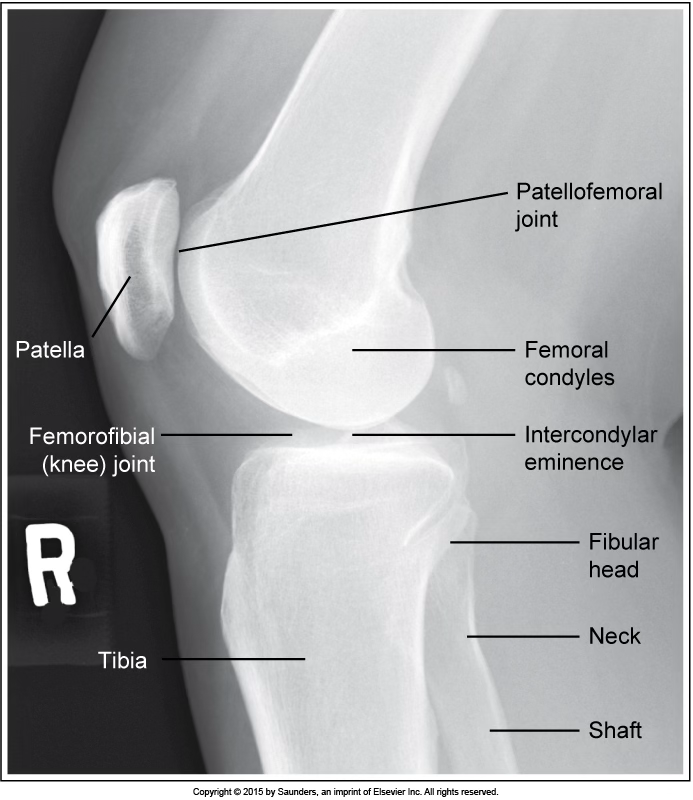

lateral knee

accurate positioning